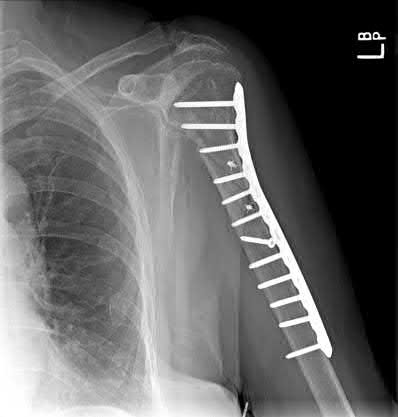

Figure A is a radiograph of an 80-year-old woman who sustained a closed injury to her left arm 10 months ago. She presents to office today complaining of persistent pain in her arm. What is the most likely metabolic or endocrine abnormality contributing to this patients presentation?

Figure A is a radiograph showing oligotrophic nonunion of a proximal third humeral shaft fracture. The most likely underlying metabolic or endocrine abnormality with this presentation is vitamin D deficiency.

The etiology of fracture nonunion is multifactorial. Predisposing factors include: mechanical instability, poor bone-to-bone contact, infection and biological/biochemical factors. A variety of other contributing factors, such as cigarette smoking and malnutrition, have also been described. Correctable metabolic or endocrine abnormalities are common in elderly patients and are considered contributory in the etiology of fracture non-union. Correction of these abnormalities should be considered prior to surgical fixation.

Brinker et al. studied 37 patients with fracture nonunions with identifiable metabolic or endocrine abnormalities. The distribution of nonunion types at the 46 sites were: oligotrophic (23), atrophic (12), infected (7), and hypertrophic

(4). They showed that 85% of patients had a previously undiagnosed metabolic or endocrine abnormality. The most common newly diagnosed abnormality was vitamin D deficiency in 25 of the 37 patients (68%).

Illustrations A and B show open reduction internal fixation of Figure A with a proximal humeral plate.